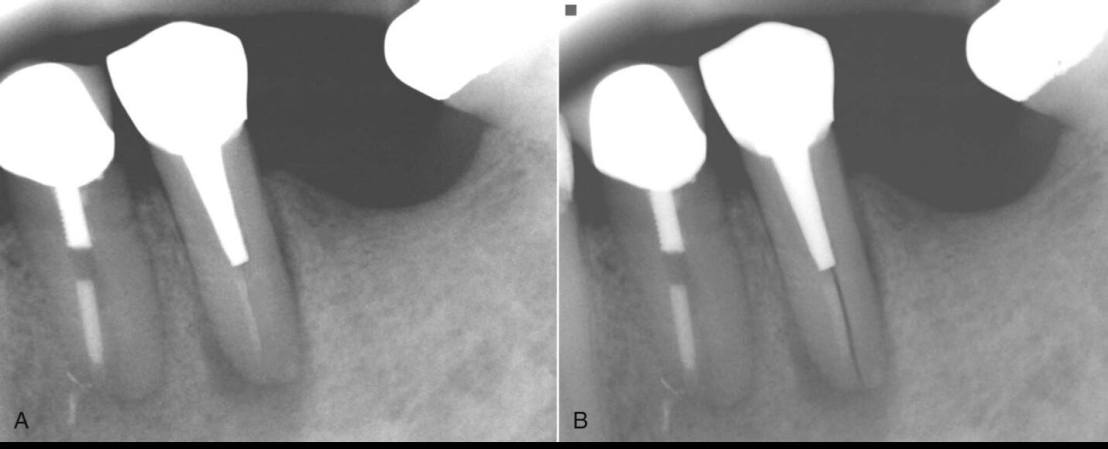

แสดงตัวอย่าง Case study